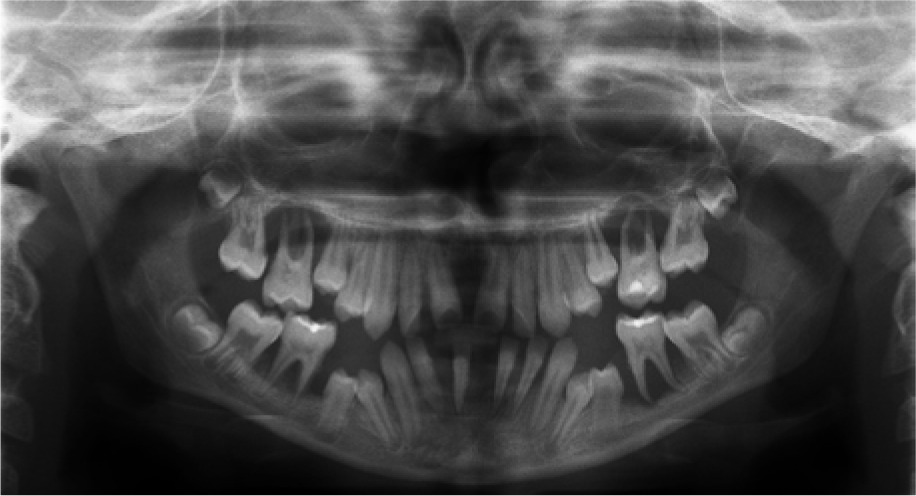

When the patient was 10, the exposure of two-thirds of palatal roots and third-degree loosening of teeth were observed (Fig. 3). A panoramic radiograph picture was taken (Fig. 4), which revealed complete absence of the bone base in all permanent first molars. Teeth 16 and 26 were qualified for extraction, which was performed in an outpatient setting under local anesthesia and antibiotic treatment (clindamycin, 10 mg/kg/dose). The obtained material from granulomatous lesions was submitted for histopathological examination, the results of which indicated non-specific inflammatory granulation tissue.